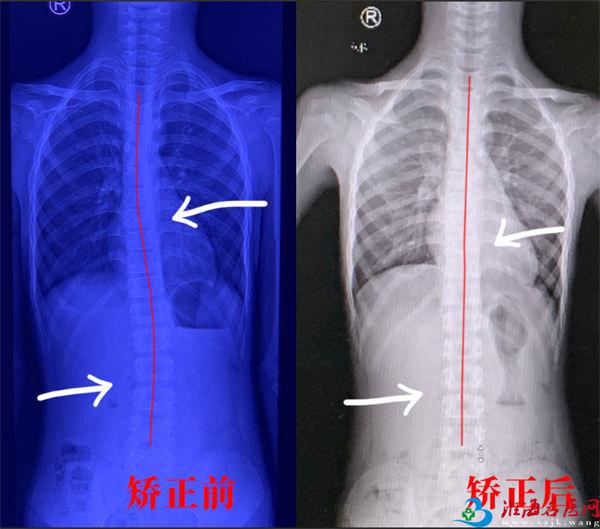

训练一个月前后脊柱形态对比图